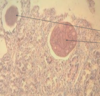

Eimeria Cameli

Thick wall with well seen cap

Eimeria Cameli

Thick wall and well seen cap

Oocysts in a camel

Thicker walls seen for survival in desert like conditions

Coccidiosis of ruminants

Oocysts in a camel

Thicker walls seen for survival in desert like conditions